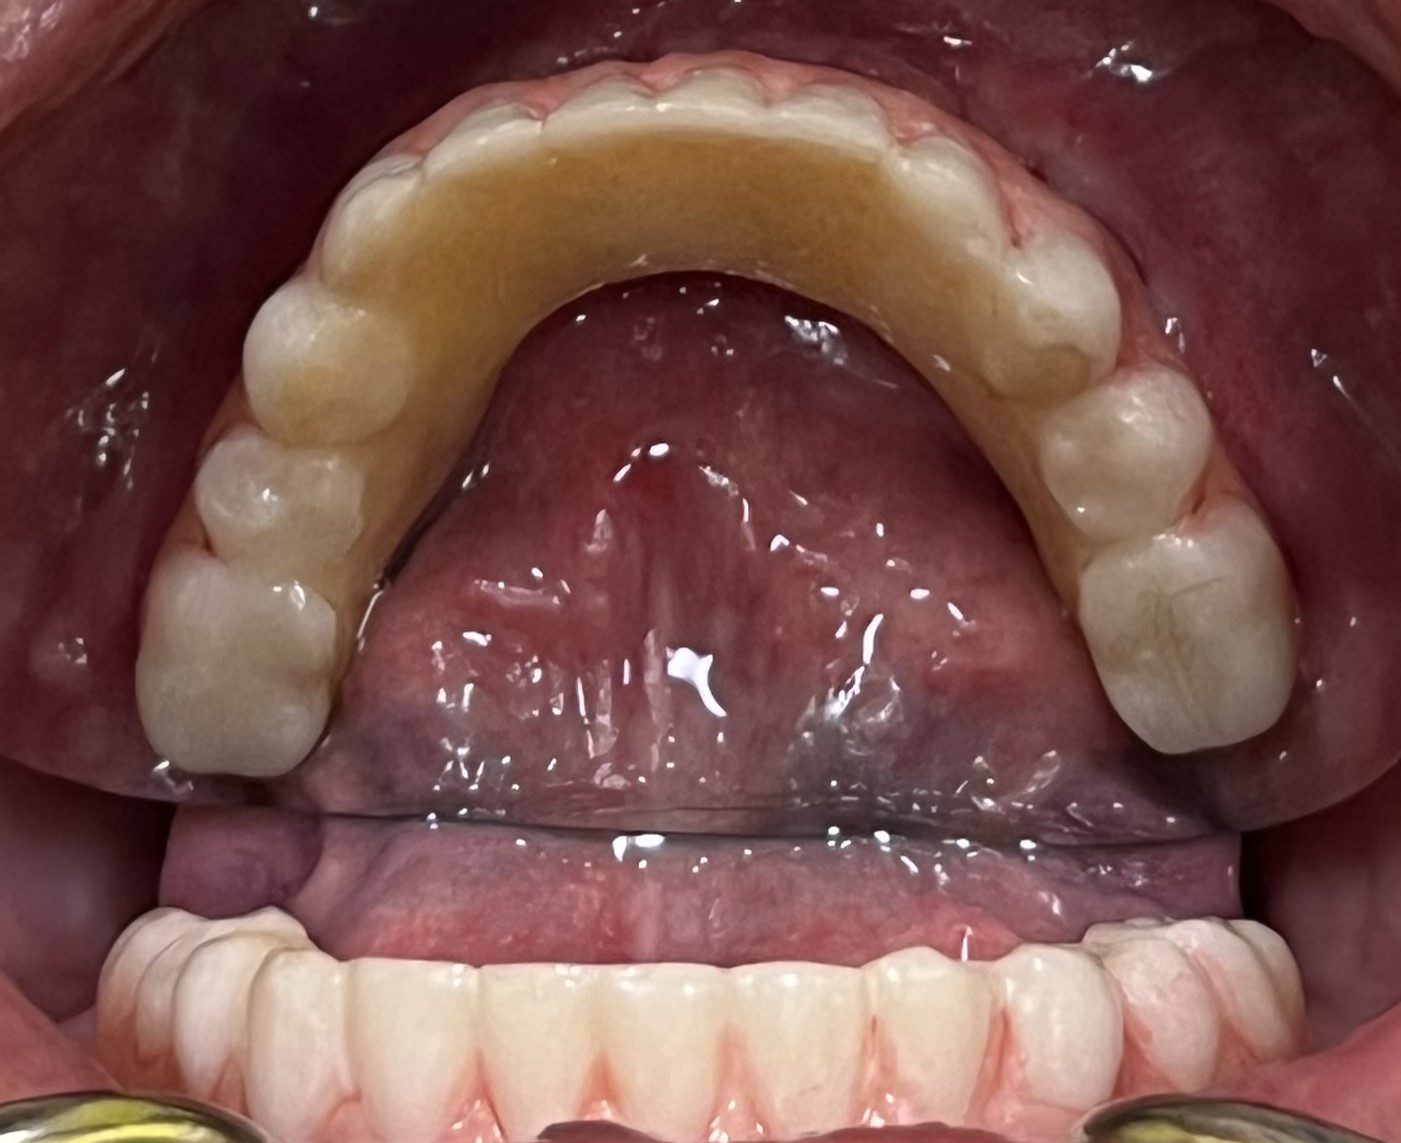

At Greenwood Dental Partners in Hudson, we use advanced imaging and 3D scans to assess bone support, spacing, anatomy, and overall oral health before recommending any treatment. Some patients may benefit from the added stability of All on 6, while others may be better suited for All on 4 based on factors like bone levels and implant positioning. These decisions are always guided by what is medically appropriate, never by cost.

The number of implants used typically ranges between 4 and 6 and is selected after a thorough clinical evaluation. Your provider considers important factors such as bone health, jaw structure, bite forces, spacing, and overall oral condition when determining whether 4 implants or 6 implants are most appropriate.